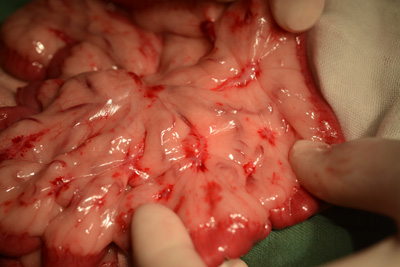

当院での症例のご紹介 みなみ野動物病院 八王子みなみ野。

Case50 試験開腹で反応性肉芽組織と診断された腹腔内腫瘤の犬の1例 –つつじヶ丘動物病院東京都調布市の動物総合病院。一般診療、循環器科、腫瘍科など。

Case50 試験開腹で反応性肉芽組織と診断された腹腔内腫瘤の犬の1例 –つつじヶ丘動物病院東京都調布市の動物総合病院。一般診療、循環器科、腫瘍科など。